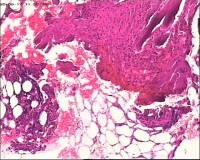

臀部组织,请帮忙看看,谢谢

性别

男

年龄

20岁

临床诊断

一般病史

藏毛窦或囊肿切开术

标本名称

臀部

大体所见

灰白灰黄碎组织一堆,大小为6.5*4*1cm。

描述诊断炎性病变